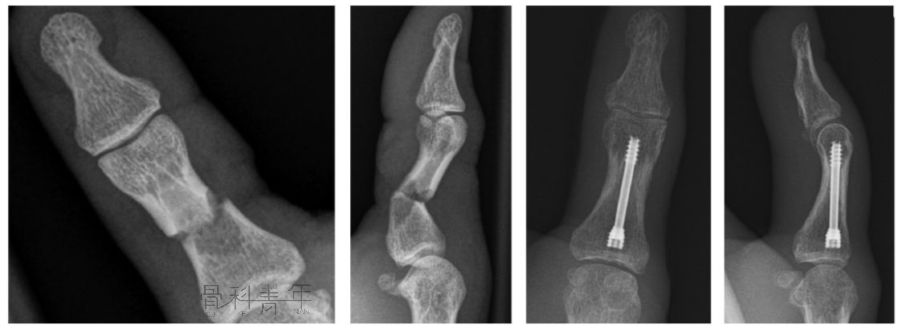

近端指骨骨折

1.经关节内技术手术方法:在 MCP 关节上作一 3.0mm的切口。MCP关节屈曲70°,在透视下自 MCP 关节背侧插入一根导丝。为方便导线的插入,将近节指骨的基部推向背侧、形成背侧半脱位。由于关节囊和副韧带的收紧,MCP关节的90°屈曲位可以防止近节指骨的背侧移位。然后将线沿其纵轴推进到近节指骨的基部。然后插入 3.0 mm 或 2.2 mm 无头加压螺钉(图 3)。在 MCP 关节半脱位困难的情况下,导丝也可以在不侵犯关节的情况下,在近节指骨基底部斜行插入。

图3 近节指骨的顺行无头加压螺钉(IMCS)固定。2.顺行经关节技术当近节指骨无法实现足够的背侧半脱位导丝位置不理想时,建议采用经关节技术。在MCP上作一长3.0mm的切口,屈曲 90°。导丝插入掌骨头的背侧。然后将导丝通过掌骨推进到近节指骨的远端(图 4)。

图4 近节指骨顺行髓内无头加压螺钉 (IMCS) 固定的经关节技术(通过掌骨头)。该技术的缺点在于会损伤掌骨头的软骨和近节指骨的基底部

图5 经关节内与顺行经关节固定模式图。3.逆行经关节内技术除顺行置入螺钉外,也可通过近指间关节逆行置入IMCS。在屈曲 90° 的近端指间 (PIP) 关节上做一个 3.0 mm的切口。然后将导丝沿其纵轴推进到近节指骨的基底部(图 6)。该技术操作较为简单,但同样存在损伤指骨远端关节面软骨风险,同时容易损伤伸肌腱

图6 近节指骨的逆行IMCS 固定。4.双顺行经关节内技术与掌骨类似,粉碎的指骨骨折采用单一加压螺钉固定同样有固定不牢靠风险。对这一类骨折,类比掌骨骨折的“Y” 型支撑技术,可采用双顺行IMCS固定(图 7) 。手术方法:在 MCP 关节上做一个横向切口,然后屈曲 70°。将指骨的近端向背侧半脱位,以便在透视下插入第一根导丝。然后可以在与指骨的长轴倾斜的方向上插入第1根导丝。最后,将第二颗螺钉置于更倾斜的方向,且螺钉长度需更短。我们通常使用2枚2.2 mm无头加压螺钉。

图7 双顺行经关节内固定近节指骨骨折。

对于粉碎的近节指骨骨折,如加压过度可能导致短缩,也可采用单枚螺钉固定。

图8 近节指骨粉碎骨折的单枚螺钉固定。